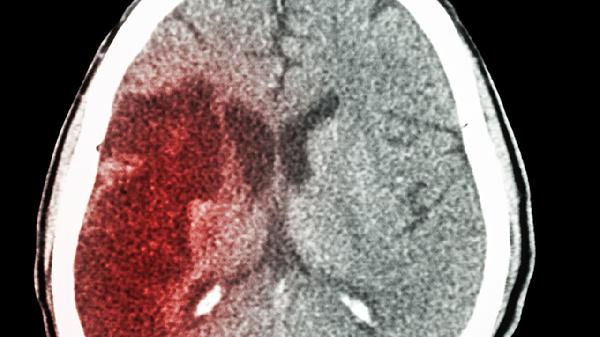

山茱萸为山茱萸科植物山茱萸的干燥成熟果肉,含山茱萸苷、莫诺苷等成分。具有补益肝肾、涩精固脱的作用,中医常用于治疗眩晕耳鸣、腰膝酸软。现代研究发现其可能通过抑制乙酰胆碱酯酶活性来改善认知功能,对脑缺血再灌注损伤有保护作用。